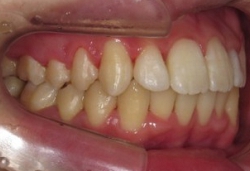

(その2)↑.

このケースは,下顎が横(右側)に大きくズレていて,上顎の歯並びに凸凹もみられます.

↑スプリント療法と,マルチブラケット矯正を併用して治療を行いました.下顎にオクルーザルスプリントを使用しながら,上顎の歯列アーチの拡大および個々の歯の整列を行った結果,下顎の右方偏位は改善し,上下の歯列の正中はほぼ一致するようになりました.